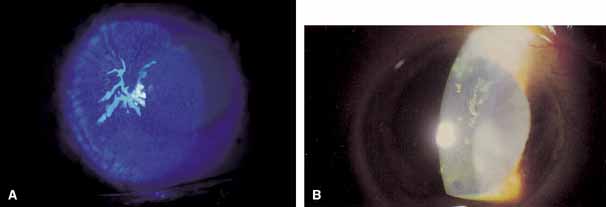

in approximately 8% of patients with HZO.64 Corneal mucous plaques may be seen in isolation or in association with

limbal hyperemia and iridocyclitis (Fig. 11A). In areas of mucous-plaque formation, the cornea appears

edematous and desquamated (Fig. 11B). These pleomorphic plaques tend to wander over the surface of the

cornea.61 The chronic coarse mucous plaques of herpes zoster are elevated and associated

with diffuse anterior stromal haze.65 These lesions demonstrate poor fluorescein staining but vivid staining

with rose bengal dye.50 Debridement of these plaques is not associated with any damage to the

underlying epithelium, and steroids have little or no effect.61 Delayed corneal mucous plaques are typically culture-negative and

result from immune, neurotrophic, or abnormal epithelial phenomena.65,68,69 Soft contact lenses, lubrication, steroids, acetylcysteine, and antivirals

have been therapeutically inconsistent.55,62,64,67,68,69 Pavan-Langston and colleagues66 found VZV DNA by polymerase chain reaction (PCR) assay in some

cases of delayed herpes zoster mucous plaques and pseudodendrites, suggesting

an infectious association. Chern and co-workers67 described a chronic form of dendritic herpes zoster epithelial keratitis

in acquired immune deficiency syndrome (AIDS).  Fig. 11 A. Herpes zoster corneal mucous plaque, stained with fluorescein. B. Chronic epithelial plaque in herpes zoster ophtalmicus. Fig. 11 A. Herpes zoster corneal mucous plaque, stained with fluorescein. B. Chronic epithelial plaque in herpes zoster ophtalmicus.